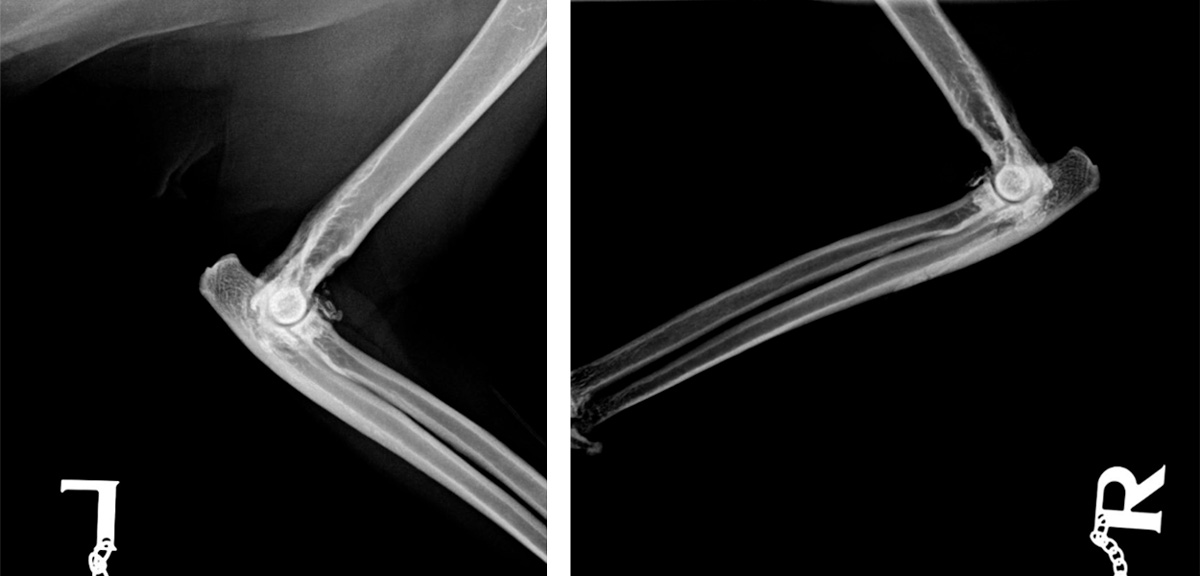

Diagnosis relies upon demonstration of radiographic changes within the joints however there are clinical signs that increase the likelihood of osteoarthritis.

The most common sites in cats are the lower back, hips, knees, ankles and elbows. Symptoms are often detected in older cats however cats as young 1 year old can have structural damage due to osteoarthritis.